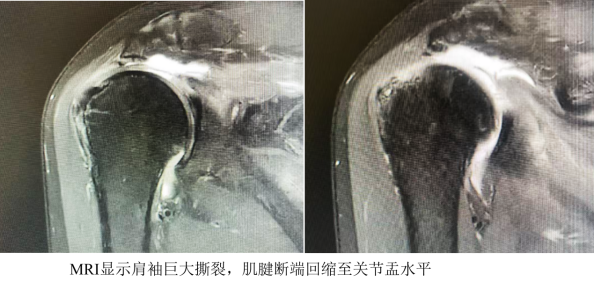

据了解,患者丽阿姨两周前意外摔伤右肩,出现剧烈疼痛且上肢活动受限,在老家就医时未明确诊断,经针灸、药物治疗后症状无改善。随后转诊至深圳某三甲医院,通过MRI检查确诊为“右肩巨大肩袖撕裂”,撕裂口直径超5厘米,肌腱断端已回缩至关节盂水平,接诊医生建议实施肩关节置换手术。考虑到传统置换手术创伤大、恢复周期长,患者及家属希望寻求更微创的治疗方案,最终慕名前往深圳二院龙华医院运动医学科就诊。

深圳二院龙华医院运动医学科钟名金博士后团队接诊后,结合患者年龄、伤情及影像学评估结果综合研判:患者虽肩袖撕裂范围大、肌腱回缩明显,但属于新鲜损伤,肌腱质量良好,脂肪化程度较轻(Goutalliar Ⅰ-Ⅱ级),具备微创修补的手术条件,无需进行创伤较大的关节置换。在向患者详细讲解病情及手术方案,并展示既往同类成功案例后,患者最终决定接受“关节镜下肩袖修补术”。